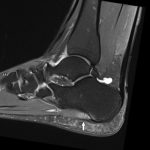

Ayak bileğinin merkezi, talus adı verilen bir kemiktir. Talus kemiği, ayak bileğinin büyük bacak kemiği olan tibia’nın kıkırdak üzerinde sürtünmesine olanak sağlayan büyük bir kıkırdak kaplamaya sahiptir. Bu iki kemik bir araya geldiğinde ayak bileği eklemi oluşur. Ayak bileğinin dış tarafında, fibula adı verilen daha küçük ve daha ince bir kemik bulunur. Bu kemik, tibianın dışa kaymasını önlemeye yardımcı olur.

Ayak bileği eklemi dengesinden bahsederken, ayak bileğinin merkezi talus kemiğini yerinde tutabilme yeteneğine bağlı olarak kısaca açıklanabilir. Ayağımız düz zemindeyken eklemimizin daha dengeli olduğunu hissederiz ve düşünürüz. Ancak, ayak parmakları aşağıya doğru yönlendirildiğinde, ayak bileği denge kaybı ihtimali ortaya çıkar bunun nedeni de eklemi dengede tutan kemiksel sınırlar arası mesafenin açılmasıdır. Bu nedenle, ayak bileği, ayak parmakları aşağıya yönlendirildiğinde daha fazla özellikle bağlara dayanarak dengesini korumaya çalışır.

Bir ayak bileği burkulduğunda, genellikle ayak parmakları ve ayak bileği eklem çizgisinin yöneliminin aşağıya doğru olduğunu görürüz.Bununla birlikte, ayak bileği herhangi bir pozisyonda iken burkulabilir. Ayak bileğini yerinde tutan altı ana yumuşak doku yapısı vardır. Bunların dördü ayak bileğinin dış tarafında yer alır ve hepsi fibulaya bağlanır. Bu nedenle, bu dört bağın hepsinde fibula kelimesi bulunur. Ayak bileğinin en sık yaralanan bağı Anterior (ön) Talo-Fibular Bağ olarak adlandırılır ve kısaltması ATFL’dir. Bu, ayak bileği burkulmalarında en sık yırtılan bağdır. İkinci en sık yırtılan bağ, topuk kemiğini fibulaya bağlayan Calcaneo-Fibular Bağdır. Üçüncü bağ, fibulayı talusun arkasına bağlayan Posterior (arka) Talo-Fibular Bağdır. Fibulaya bağlanan dördüncü bağ, fibulayı tibiaya bağlayan Tibiofibular Sendesmotik Bağdır. Ayak bileğinin önünde bulunan yumuşak doku, ayak bileği eklem kapsülüdür ve diğer bağlara ek olarak ayak bileğinin kaymasını önlemeye yardımcı olur. Bir diğer denge ve stabilizasyon bağı ayak bileğinin iç tarafında bulunur. Yunan harfi delta gibi üçgen şekli oluşturduğu için bu bağa Deltoid Bağı denir. Deltoid bağı tibiayı talusa bağlar.

Bazen ayak bileği etrafındaki kemikler kırılabilir. Genellikle daha küçük olan dış kemik olan fibula kırılır. Bununla birlikte, daha büyük kuvvetlerle ayak bileği etrafındaki hem fibula hem de tibia kırılabilir. Ayak bileği etrafındaki kemikler kırıldığında ciddi bir istikrarsızlığa neden olabilir ve hatta ayak bileği eklemi çıkabilir. Bazı durumlarda, ayak bileği hafifçe yerinden oynar, bu duruma subluksasyon denir. Bir doktor kırık veya çıkık teşhisi koyarsa, ayak bileğinin fonksiyonel olarak iyileşmesi için cerrahi önerilebilir.